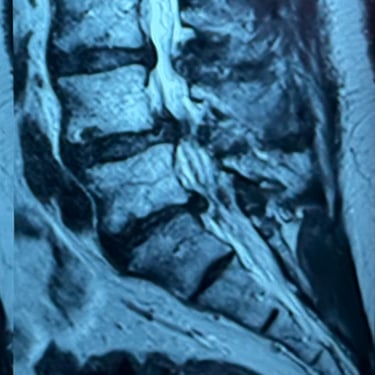

Columna lumbar inestable con listesis: tratamiento con artrodesis y tornillos transpediculares

La listesis lumbar ocurre cuando una vértebra se desplaza hacia adelante o hacia atrás respecto a la vértebra inferior, generando inestabilidad de la columna lumbar. Esta condición puede causar dolor lumbar crónico, compresión nerviosa, ciática, debilidad en las piernas o dificultad para caminar. Cuando el tratamiento conservador no es suficiente, la artrodesis lumbar con tornillos transpediculares es una alternativa quirúrgica eficaz. Este procedimiento permite fijar las vértebras afectadas mediante implantes que estabilizan la columna y favorecen la fusión ósea. Con técnicas modernas y abordajes mínimamente invasivos, se logra aliviar el dolor, mejorar la estabilidad vertebral y recuperar la función del paciente.